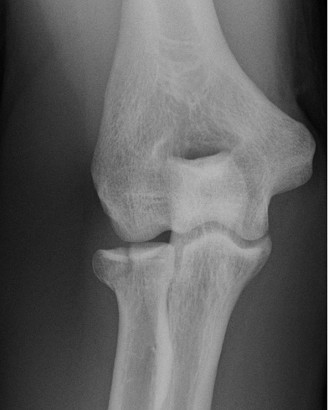

Examination reveals deformity about the elbow with no open lesions or skin tenting. He has a palpable radial and ulnar pulse and is neurologically intact. His images are shown (Figs. 2–85 to 2–88).

Figure 2–85

Figure 2–86

Figure 2–87

Figure 2–88

What is the diagnosis and direction of displacement?

The correct answer is (B). This is the most common type of elbow dislocation, and often does not cause any osseous injury. Posterolateral and posteromedial dislocation account for approximately 90% of dislocations. Adequate pre- and postreduction films are necessary to evaluate for fracture, which would change the classification to a complex injury.